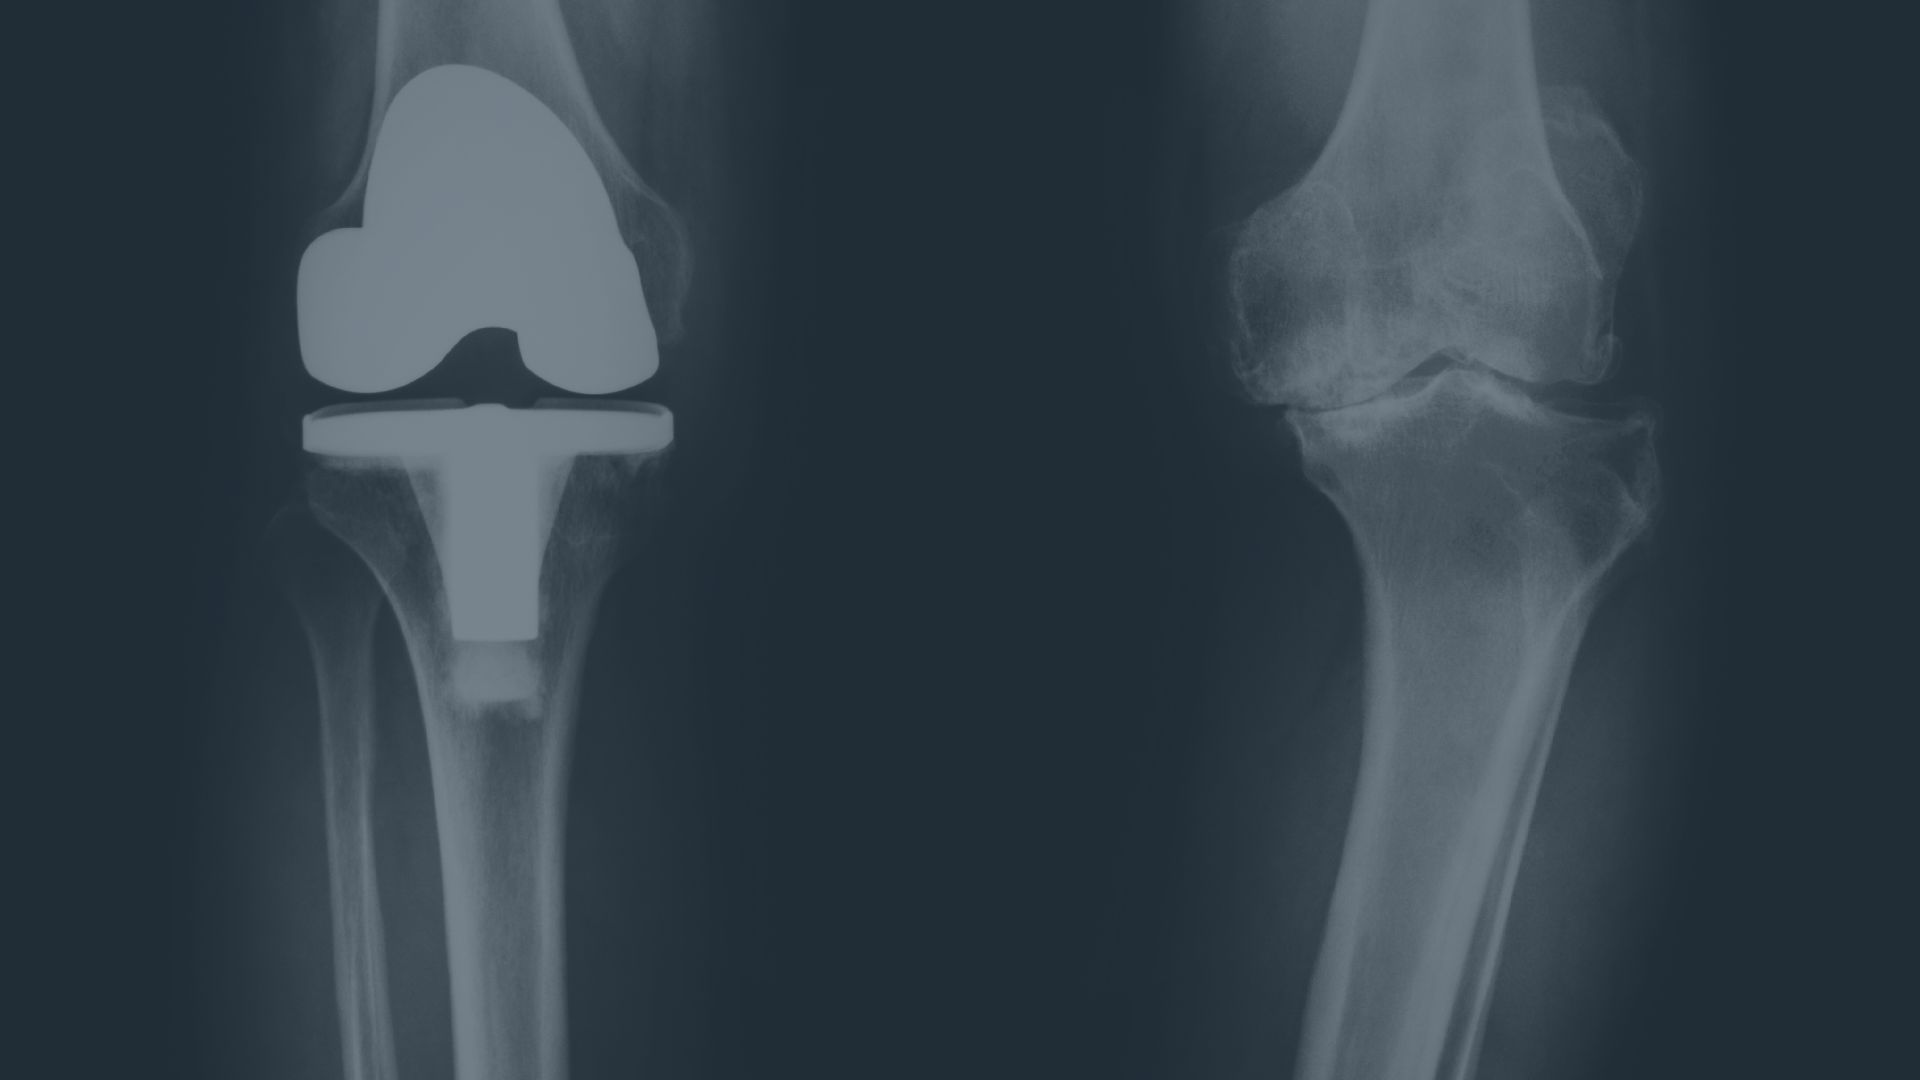

Osteoarthritis: Degeneration, & Repair

Learn what truly drives joint degeneration, how inflammation accelerates damage, and how nutrition influences long-term repair and resilience.

Learn More About This